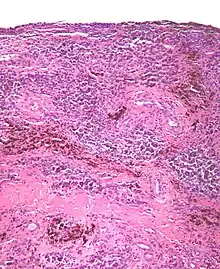

| Micrograph of diffuse TGCT, also known as pigmented villonodular synovitis. H&E stain. | |